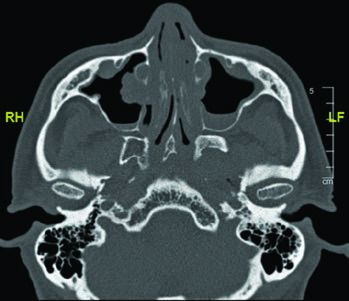

Skull base structure delineation must be performed using bone windows on CT. Key landmarks include: the foramen ovale (red), cochlea (blue), vestibule (orange), internal auditory canal (violet), and semicircular canals (green). Correctly identifying these structures is critical for ensuring adequate neural pathway coverage without excessive irradiation of sensitive structures such as the cochlea.

My recommendation is to contour these structures as organs at risk before expanding the CTV toward the skull base. This makes it possible to objectively evaluate dose-volume relationships and make conscious decisions about how much coverage is truly needed versus the cost in auditory or neural toxicity. A similar approach is used in nasal cavity and paranasal sinus delineation, where the skull base also plays a central role.